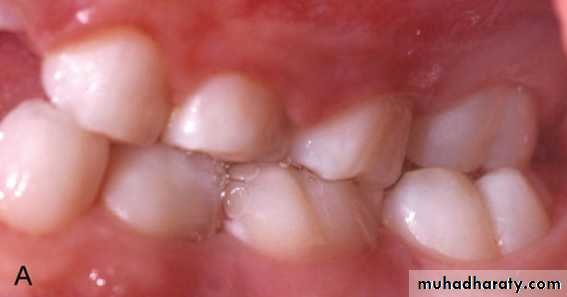

Unilateral crossbite: may be associated with mandibular shift on closure or less frequently may result from true arch asymmetry.

Unilateral posterior crossbite with lateral shift may result from:

• Occlusal interferences from primary canine: there is normal occlusal relations at initial contact but in centric occlusion there is mandibular shift leading to unilateral crossbite.

Initial contact

Centric occlusion